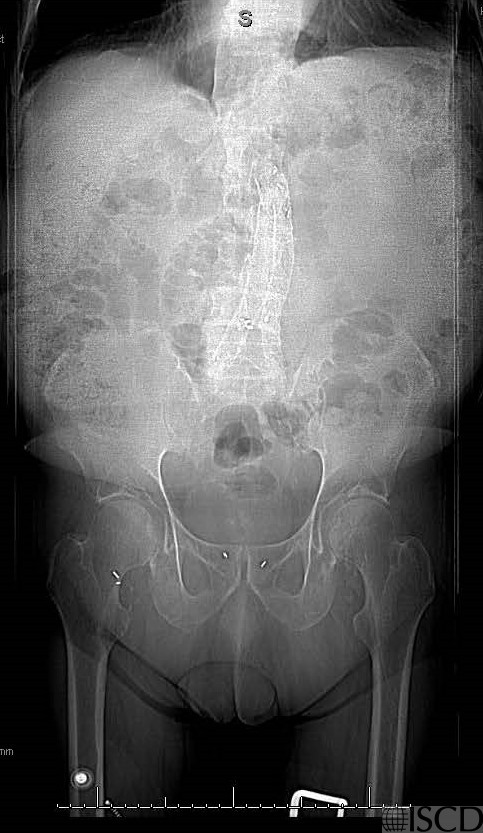

This is the accompany radiograph to the lumbar spine DXA scan.

There is an endovascular stent with endograft in both common iliac arteries. Because the internal artifacts overly the lumbar spine, the involved levels should be deleted, meaning that th spine will not be a location for diagnosis and monitoring since only one vertebral level is left.

There is an endovascular stent with an endograft in both common iliac arteries. When the findings overlap the spine, the spine will not be a location for diagnosis and monitoring.